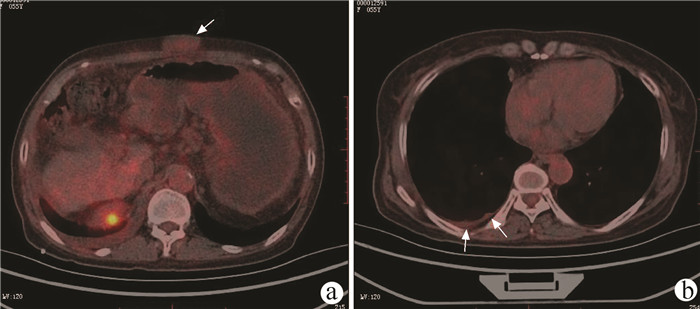

Standard for diagnosis and treatment of primary liver cancer (2022 edition)

General Office of National Health Commission

2022, 38(2): 288-303. DOI: 10.3969/j.issn.1001-5256.2022.02.009

Abstract(4828) HTML (9696) PDF (3290KB)(2813)